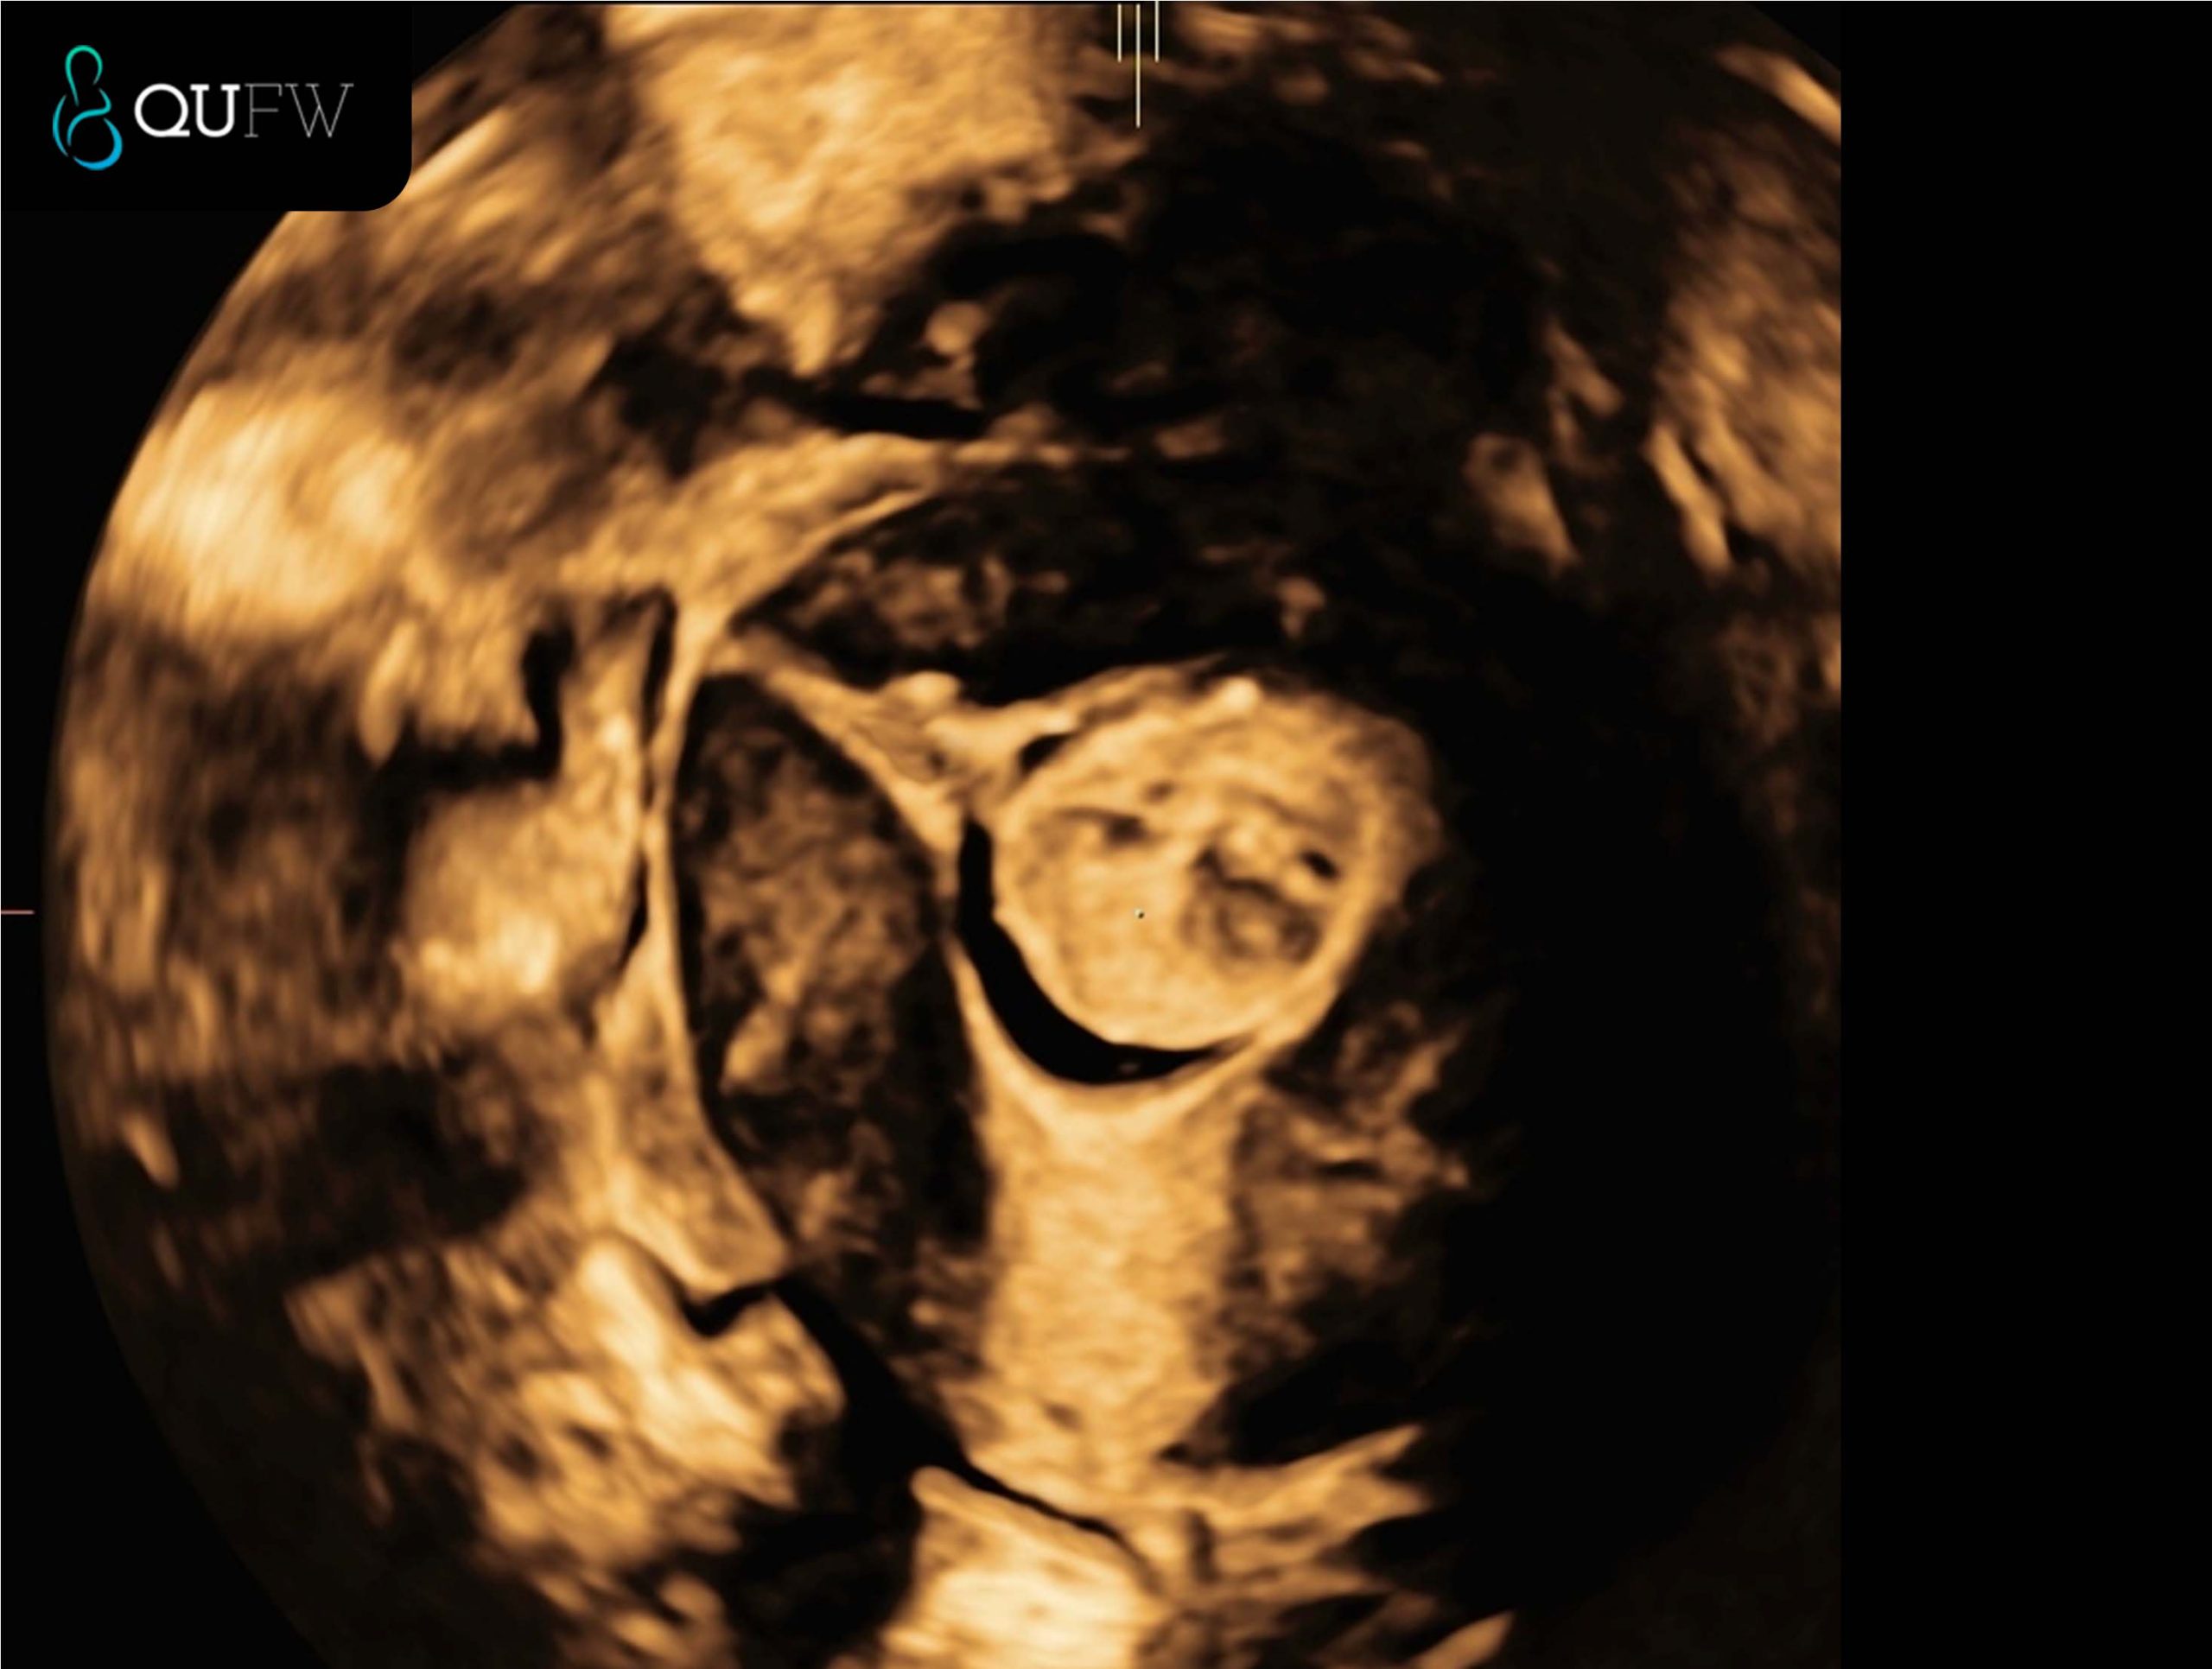

Saline Infusion Sonography (SIS) showing a 3D coronal reconstructed image of a submucosal fibroid